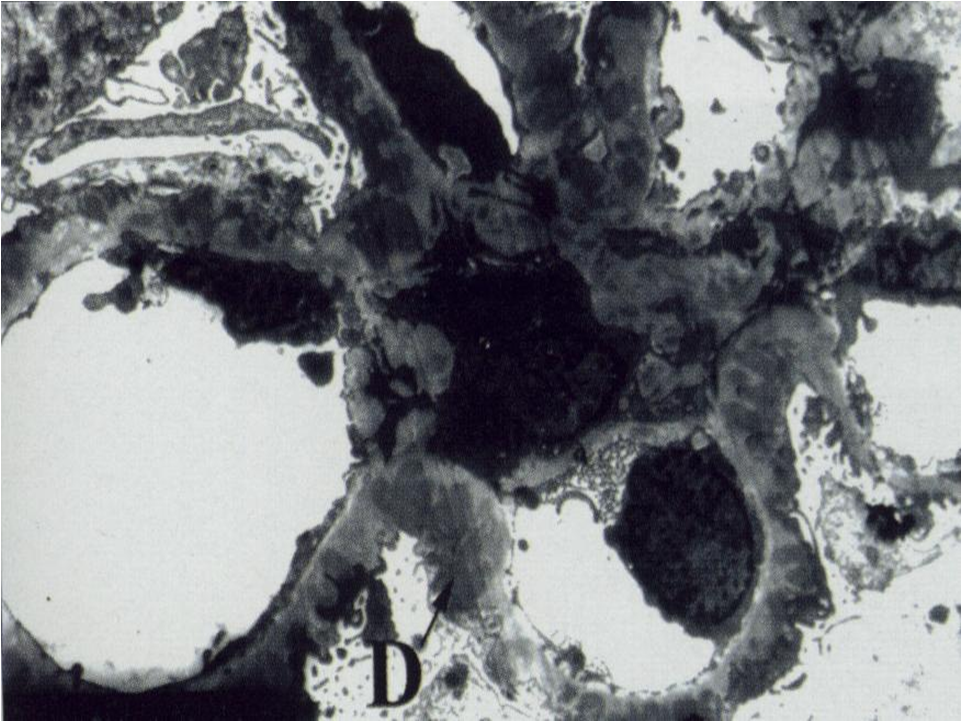

电镜下系膜区和内皮下可见电子致密物沉积(图5-4-3)。 该病理类型约占我国原发性NS的10%~20%。本病男性多于女性,好发于青壮年。约1/4~1/3患者常在上呼吸道感染后,表现为急性肾炎综合征;约50%~60%患者表现为。NS,几乎所有患者均伴有血尿,其中少数为发作性肉眼血尿;其余少数患者表现为无症状性血尿和蛋白尿。肾功能损害、高血压及贫血出现早,病情多持续进展。50%~70%病例的血清C3持续降低,对提示本病有重要意义。 本病所致NS治疗困难,糖皮质激素及细胞毒药物治疗可能仅对部分儿童病例有效,成人疗效差。病变进展较快,发病10年后约有50%的病例将进展至慢性肾衰竭。